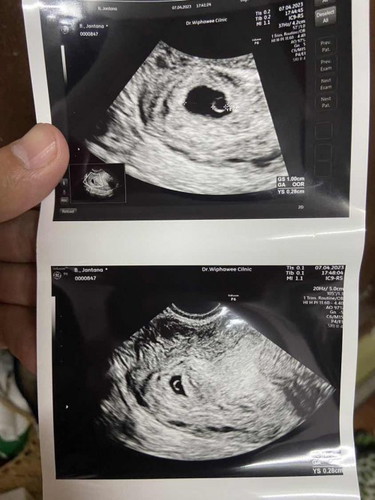

ไปฝากครรภ์ 4-5 Week

เมื่อวันศุกร์ไปฝากครรภ์ และอัลตราซาวด์มาค่ะ คุณหมอบอกว่าอายุครรภ์ประมาณ 4-5 สัปดาห์ เห็นถุงการตั้งครรภ์ มีถุงไข่แดง แต่ยังไม่เห็นน้องค่ะ นัดอีกที 18 เมษา บ้านอื่นๆมาแชร์กันบ้างนะคะ ☺️

เห็นแบบนี่เหมือนกัน แต่ภุงไข่แดงไม่ชัดแบบนี้ ซาว5wk 2dayค่ะ นีดอีกที21 เม.ย. ลุ้นๆไปด้วยกันนะคะ

อายุครรภ์ยังน้อยมากๆค่ะ ของเราเจอตัวน้องสัปดาห์ที่9เลยค่ะ